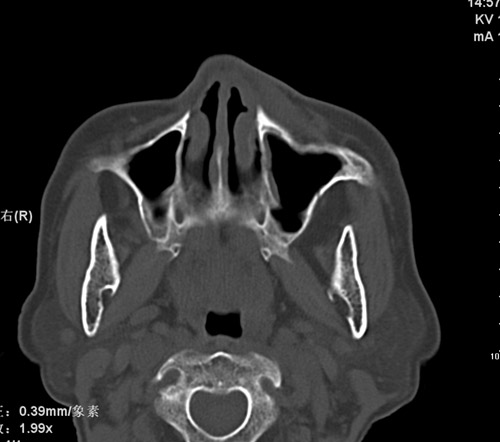

标题: CT17755:女,74 左鼻旁肿胀半年,临床以左上颌窦旁占位行CT [打印本页]

标题: CT17755:女,74 左鼻旁肿胀半年,临床以左上颌窦旁占位行CT

ct考虑鼻前庭囊肿 或鼻翼基底部慢性炎症,左上颌窦少许炎症 请指教

1)考虑左侧鼻前庭囊肿并感染。2)双侧上颌窦炎。

左侧鼻前庭囊肿并感染。双侧上颌窦炎。支持